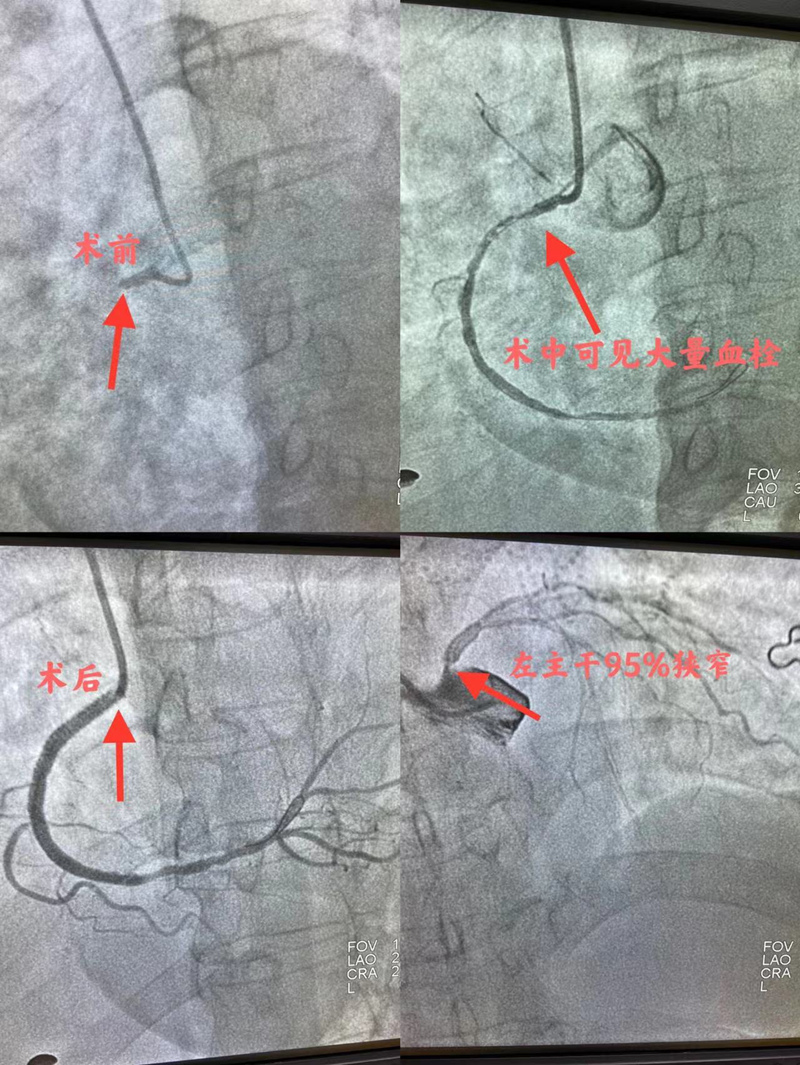

于主任团队为患者行冠脉造影发现患者左主干近段可见95%狭窄,前降支中段可见99%弥漫偏心狭窄,远段100%闭塞,D1部90%狭窄,中段80%狭窄,回旋支中段可见90%左右弥漫狭窄,右冠状动脉近段100%闭塞。于主任告知患者家属病情并征得同意后立即为患者开通本次病变血管。

时间就是生命,时间就是心肌。从患者入院到结束治疗仅用了25分钟,于右冠病变处植入支架2枚,患者胸痛症状缓解,意识恢复,血压、心率回升,病情好转,通过重症医学科观察治疗后转到心血管内二科进一步治疗,一周后康复出院。